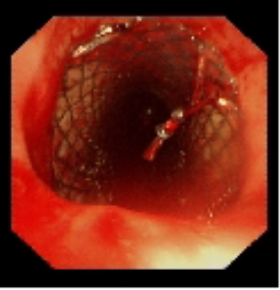

術中植入金屬覆膜支架

針對患者氣道狹窄危象,呼吸與危重癥醫學科聯合麻醉科、醫學影像科等多學科團隊制定個性化方案。術中采用全身麻醉聯合喉罩通氣,通過硬質支氣管鏡與軟鏡協同操作,在狹窄段實施腫瘤冷凍切除,隨后精準植入Y型金屬覆膜支架。手術全程動態監測生命體征,最終支架釋放位置理想,管腔擴張充分。術后復查顯示氣道通暢性恢復,患者血氧飽和度穩定在93%-97%。